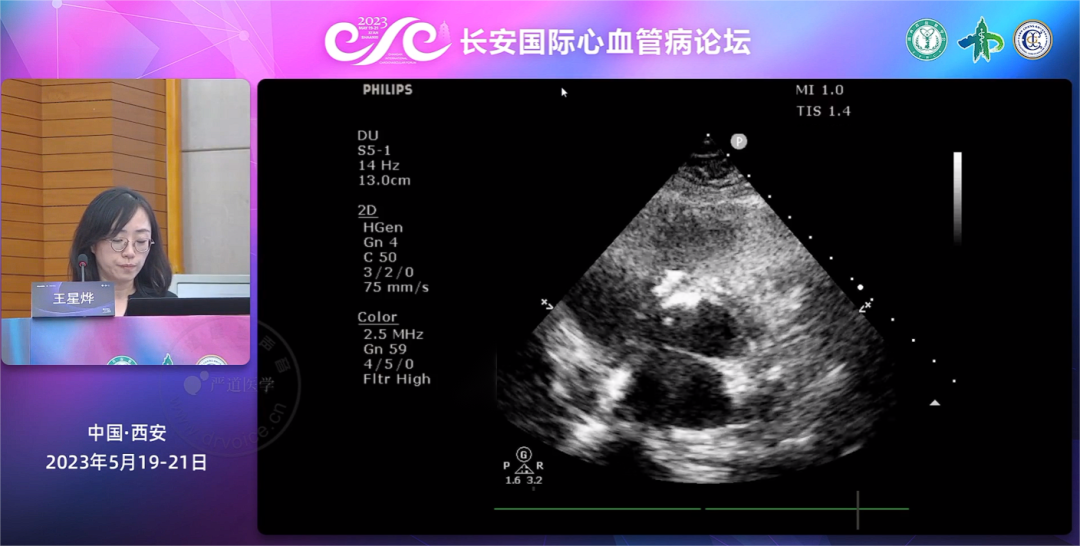

会议伊始,王星烨教授带来了两例全降解封堵手术演示,一例成人大型漏斗状膜部瘤室间隔缺损封堵,另一例成人先心病室间隔缺损修补术后残余漏封堵。理论与实践相结合,王星烨教授详细讲解了手术过程,并着重介绍了在超声引导下,创新全降解封堵器的释放原则、操作要领和注意事项。术后复查超声及造影提示,两例均无残余分流、封堵效果理想,手术圆满成功!